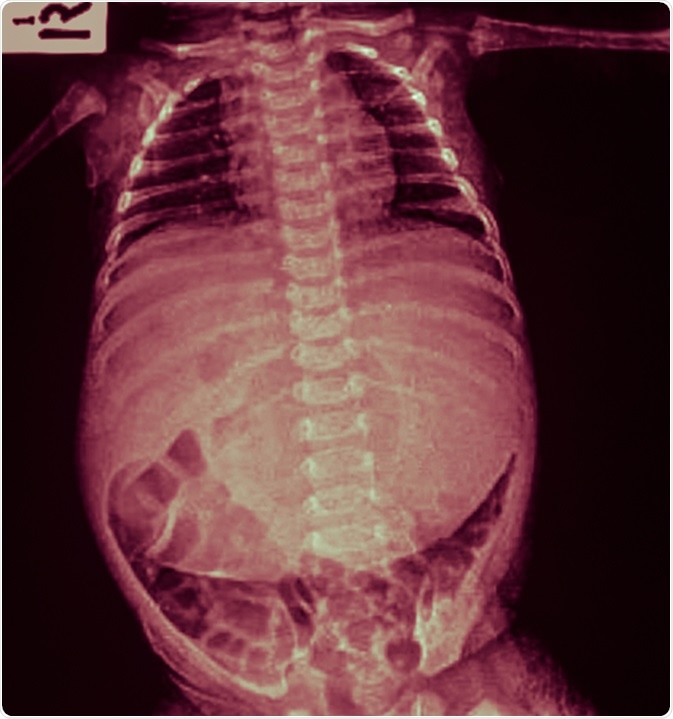

X-ray infant body and abdominal distension (flatulence, stomachache, pain). Image Credit: Tewan Banditrukkanka / Shutterstock